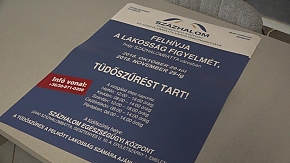

Erre biztat a százhalombattai önkormányzat, amely idén is ingyenes tüdőszűrést szervezett a városlakók részére október 29-től november 29-ig. A törökbálinti tüdőgyógyintézet mobil szűrőállomásán a Százhalom Egészségügyi Központban lehet jelentkezni hétfőn 12-től 18, kedden 8-tól 14, szerdán 12-től 18, valamint csütörtökön és pénteken 8-tól 14 óráig.

A tüdőszűrés a felnőtt lakosság számára ajánlott. Elvégzése 40 év felett évente egyszer ingyenes, a törvény által kötelezetteknek szintén térítésmentes. Az önkormányzat 3 millió forinttal járult hozzá, hogy a helyben szervezett szűrés mindenki számára kényelmesen elérhető és ingyenes legyen. Egyéb esetben térítésköteles a szűrés, például a munkahelyi alkalmassági vizsgálat részeként 1700 forint a díja. Fontos tudni, hogy a 14 és18 év közötti gyermekek vizsgálatához beutaló és szülői beleegyező nyilatkozat szükséges. A vizsgálatra személyi igazolványt, TB kártyát és – ha van – előző évi tüdőszűrőigazolást kell vinni.